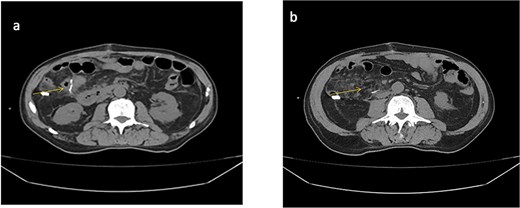

The drain output was monitored daily (Fig. 4). By hospital day 5, the output had decreased to 430 cc/day, and the fluid had become clear (Fig. 5). A soft diet was reintroduced. On day 6, repeat fluid analysis revealed a triglyceride level of 123 mg/dL, indicating resolution of the chylous leak. The patient was discharged on day 7 with outpatient follow-up.

Image of ascitic fluid on day 5 of hospitalization, showing clearer appearance indicating reduced chyle content.